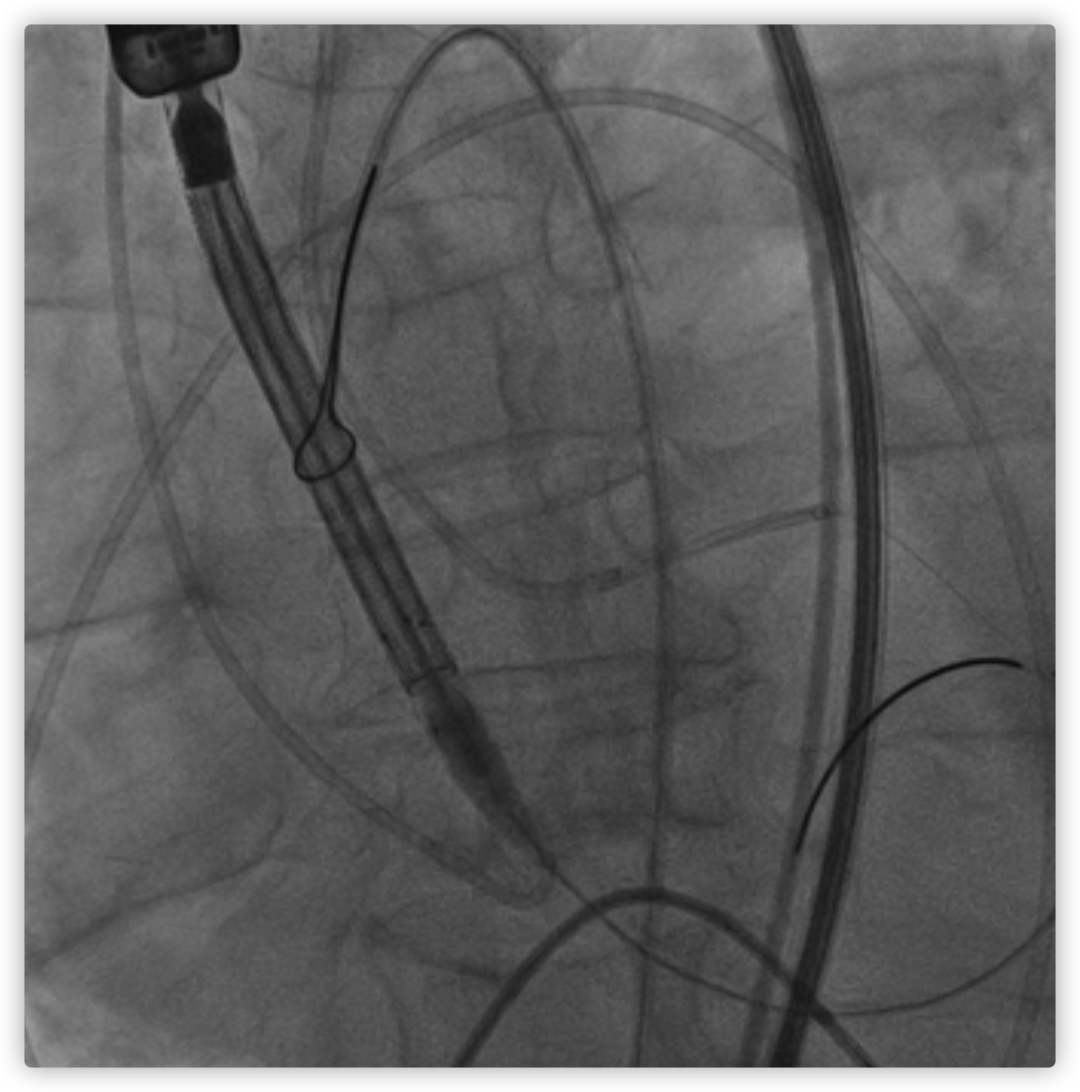

LM烟囱支架植入4.0*30mm